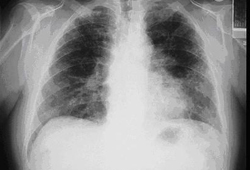

Posterior-anterior view of the chest with bibasilar linear interstitial changes consistent with asbestosis

From the personal collection of Kenneth D. Rosenman MD